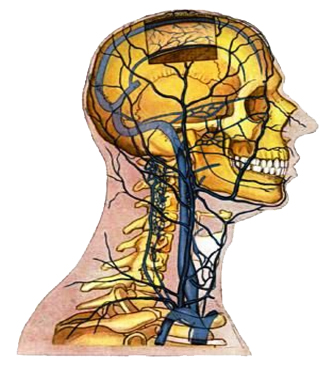

Анатомия внутренней яремной вены: КТ изображения